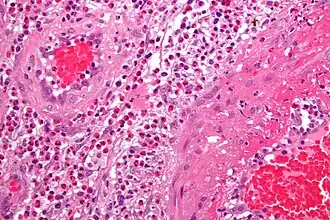

Le diagnostic définitif de vascularite est établi après une biopsie des organes ou des tissus impliqués, tels que peau, sinus, poumon, nerf et rein. La biopsie met en évidence le type d'inflammation des vaisseaux sanguins.

Exemple illustré : vascularites leucocytoclastiques